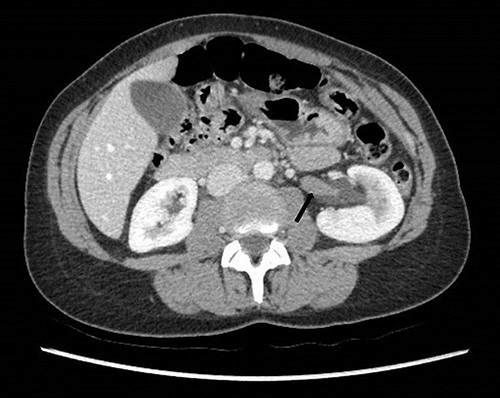

To investigate the bleeding source, she subsequently had a CT renal angiogram 3 days later that showed a narrow angle between origin of SMA and the aorta (Fig. 3) with multifocal areas of hypoattenuation throughout the left renal cortex (Fig. 4). It showed a compression ratio of 3.25 (diameter of pre-compressed vein =6.5 mm; diameter of compressed vein =2 mm) (Fig. 5).

Computed tomography on presentation showing multifocal areas of hypoattenuation throughout the left renal cortex (arrows).